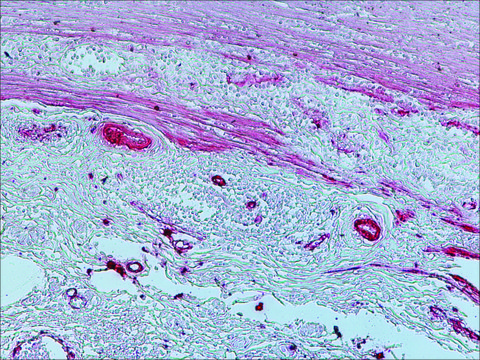

Anti-Mouse IgG (Fc specific)-Alkaline Phosphatase antibody is suitable for use in ELISA (1:1500) and western blot. The antibody can also be used for immunohistochemistry (1:40 using formalin-fixed, paraffin-embedded sections).